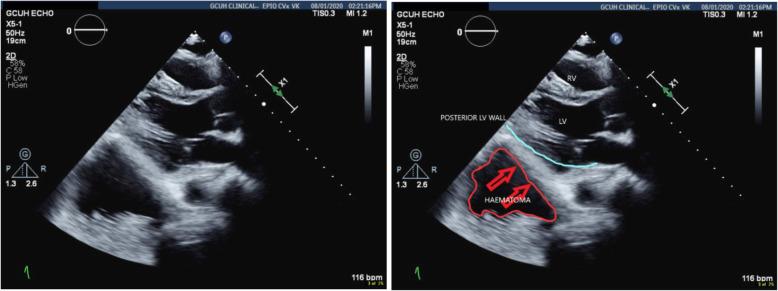

There exists a therapeutic conflict between haemorrhage control and prevention of thromboembolic events following polytrauma and complications are not uncommon. Such opposing therapies can result in unexpected pathophysiology and there is a real risk of misdiagnosis resulting in harm. This case presents a previously unreported complication of prevention and management of thromboembolism- STEMI (ST elevation myocardial infarction) and tamponade mimic secondary to retroperitoneal haematoma.

CASE PRESENTATION

We present a 50-year-old male polytrauma patient who following treatment for presumed pulmonary embolus demonstrated classical clinical findings of myocardial infarction and pericardial tamponade secondary to a retroperitoneal haematoma. This is an event not previously reported in the literature. The risk of adverse outcome by management along the standard lines of STEMI (ST elevation myocardial infarction) was averted through awareness for alternative aetiology via a multi-team approach which resulted in percutaneous drainage of the haematoma and complete resolution of symptoms.